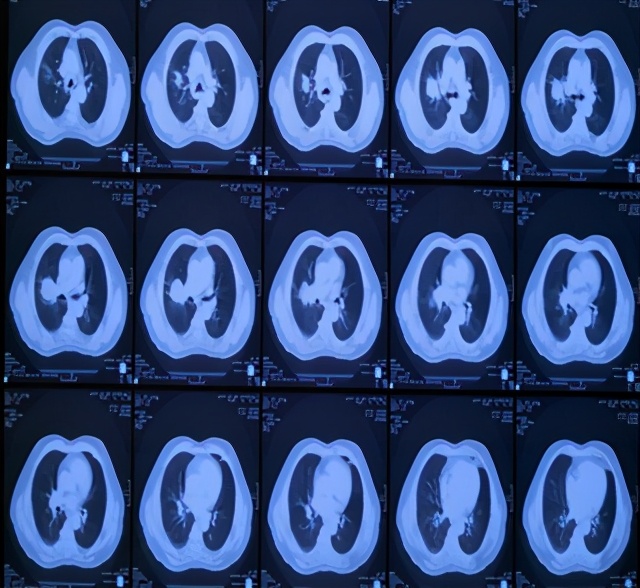

患者刘某某,男,65岁, 13年前因咳嗽、咳痰带血半年就诊,胸部CT示右上肺占位,支气管镜示右上叶前段支气管远端狭窄,活检病理:中低分化鳞癌。诊断:右上肺中低分化鳞癌,T4N1M0,IIIB期。

因二次全麻下气管插管出现哮喘无法手术,于2007年5月30至2007年6月28日进行局部放射治疗,同时给予对症支持治疗。照射剂量PTV(肿瘤外5mm)66GY/22f/30d;GTV(肿瘤边缘)70GY/22f/30d;GTV1(肿瘤内部)77GY/22f/30d;治疗期间,咳嗽缓解、无咯血,血常规 基本正常 范围,按计划完成治疗。